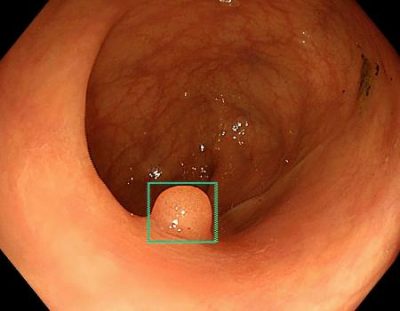

AI利用、医師の技量低下 大腸内視鏡の質検証

2025/08/13国内外ニュース 主要大腸内視鏡検査で医師が普段から人工知能(AI)の助けを借りていると、AIを使わず検査した際にポリープの一種「腺腫」の発見が約20%減るとの研究を、ポーランドなどの国際チームが13日、英医学誌ランセット関連誌に発表した。約2200人分の検査...